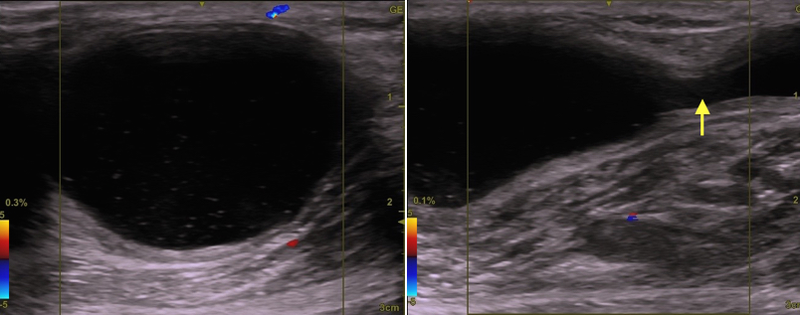

下写真のケースの場合は、矢印の所が開口部です。

右写真のエコーで確認できます(→)。その下に本体がいます。

上写真の患者さんのような癒着のない綺麗な袋(嚢腫)なら、

くり抜き(へそ抜き)術で簡単に手術ができます(下写真)。